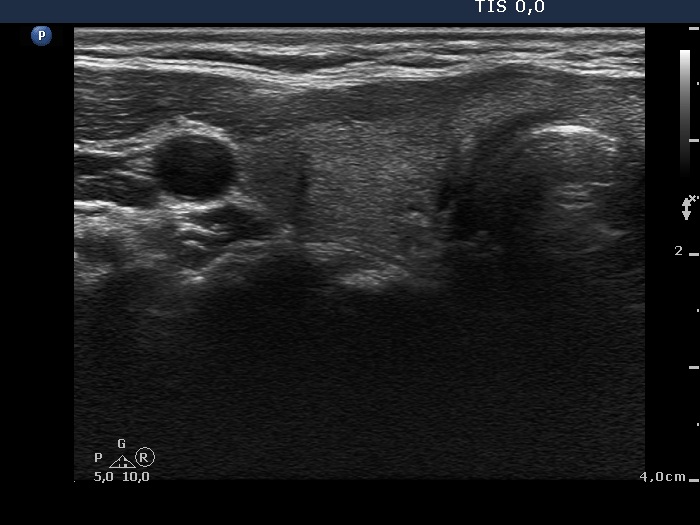

Initial examination (1st and 2nd rows of images):

Ultrasonography: there were multiple hypoechogenic areas with ill-defined borders in both lobes, primarily in the right one. The vascularization was decreased.